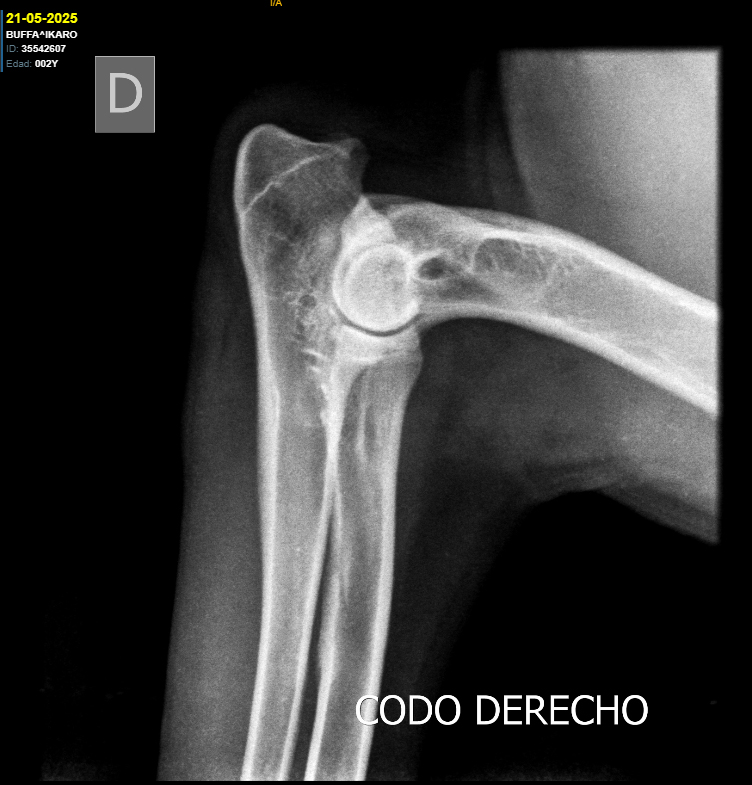

Cadera y Codos:

HD A / ED 0/0